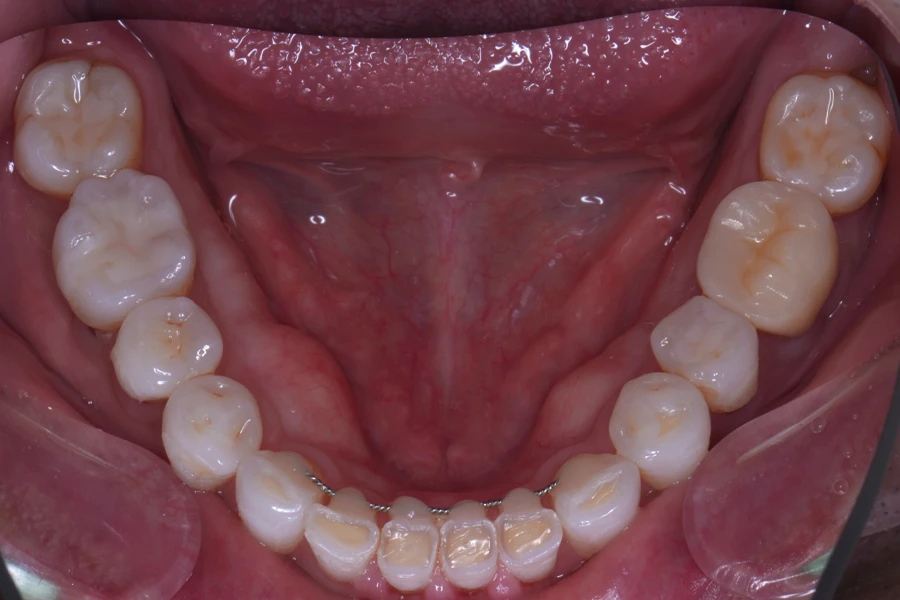

治療後